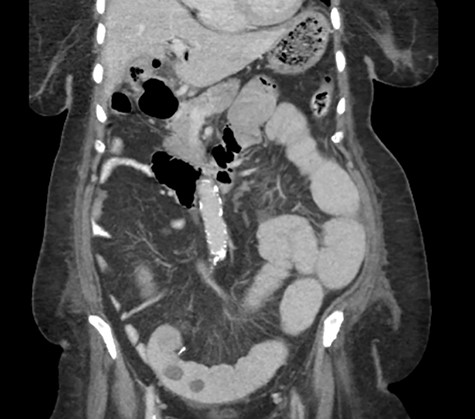

A CT abdomen and pelvis scan showing multiple large stones in the small bowel.

Postoperative course was marked by a slow recovery evidences by persistently high nasogastric tube output and failure to open her bowel. On the third postoperative day, a trial of therapeutic Gastrografin was given, not much improvement was achieved, and the patient continued to be obstructed. A repeat abdominal CT scan was obtained on day 5 due to persistence of intestinal obstruction. It showed dilated contrast-filled small bowel loops with multiple filling defects, indicating recurrent GSI (Fig. 4).